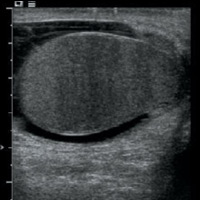

An ultrasound examination showed heterogeneously hypoechoic, mildly enlarged, diffusely hypervascular right epididymis and testes with impressively increased color and pulsed Doppler flow (Figures A, B, and C). There appeared to be multiseptated complex fluid in the right scrotum encasing the right testes and epididymis, most appreciably in the cephalad right scrotum, depicting complex reactive hydrocele/pyocele (Figure F). There also was a 1.5-cm multiloculated complex collection within the right epididymal head reflecting a small abscess (Figures D and E).

| Figure A | Figure B |

| Figure C | Figure D |

| Figure E | Figure F |